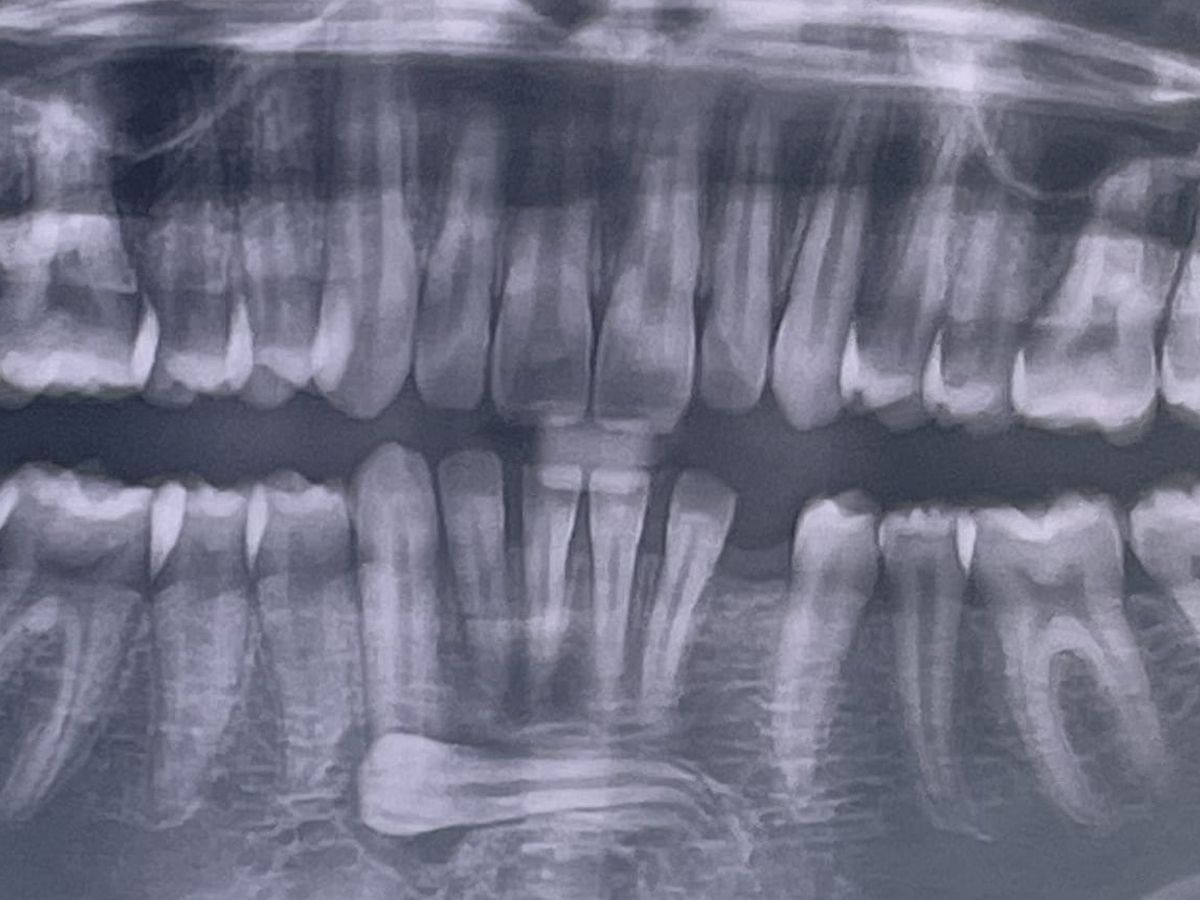

Hi, my name is Amber and I am raising funds for my son Justices oral surgery. We recently were told that one of justices adult teeth had turned sideways into his chin instead of emerging like a normal adult tooth would, as well as having an under developed lower jaw. Because of this he is now in need of oral surgery to remove the tooth that has turned along with all 4 wisdom teeth. Once his oral surgery is complete he will have to have 3 types of dental blocks/braces over 3 years, followed by upper and lower retainers night and day until he is 20 and then will need to have a dental implant placed.

If he does not have the surgery and braces started within the next year his lower teeth will push out of his lower jaw, and they will likely have to brake his jaw to help it grow instead.